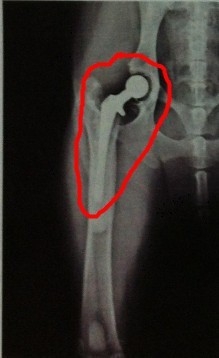

图中所示红线划分出了股骨头在髋臼内的股骨头,大约只占股骨头的1/4,属于严重的髋关节发育异常